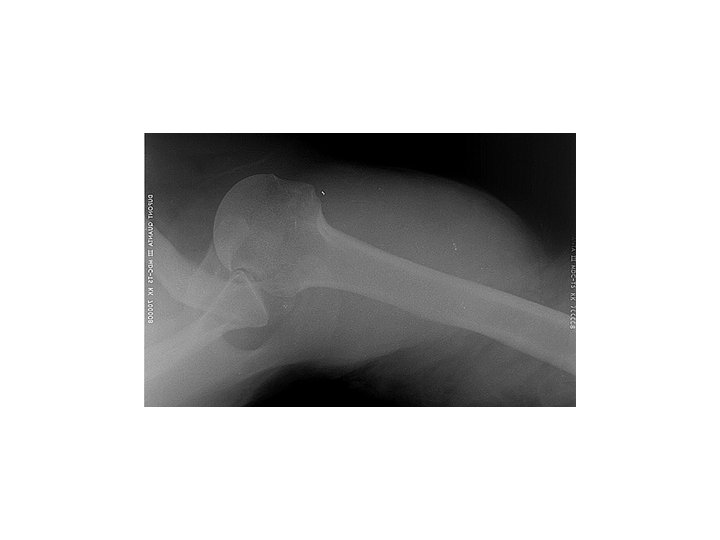

Infraglenoid Dislocation + Hill-Sachs Fracture